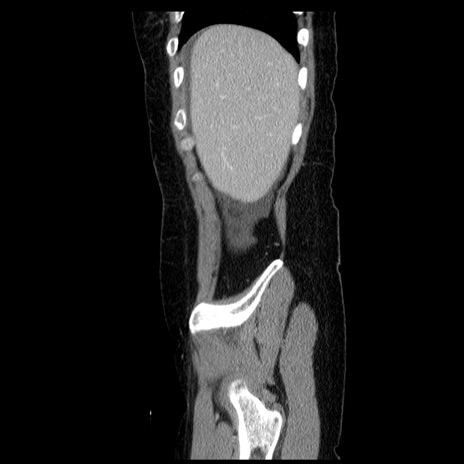

症例6(矢状断像)

【症例】50歳代女性

【主訴】下腹部痛

【既往歴】卵巣癌術後(8年前に当院で卵巣摘出)